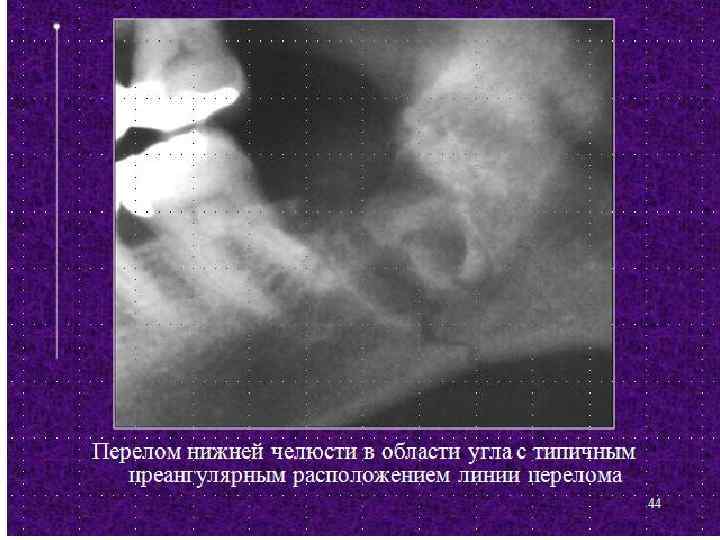

Диагноз. • Перикоронит и позадимолярный периостит диагностируют на основании характерной клинической картины и рентгенологических данных. • На рентгенограмме нижней челюсти в боковой проекции видны положения нижнего зуба мудрости, состояние его периодонта и окружающей кости, отношение к ветви и каналу нижней челюсти. • Позадимолярный периостит в отличие от перикоронита сопровождается образованием воспалительного инфильтрата в позадимолярной области. • При хроническом процессе характерна резорбция кости чаще в виде широкой щели у шейки зуба и по ходу корня, нередко в виде полулуния. Дифференциальный диагноз. • Острое воспаление при затрудненном прорезывании нижнего зуба мудрости не представляет трудностей для распознавания; • хронический перикоронит следует дифференцировать от хронического пульпита и периодонтита, в отдельных случаях – • от невралгии 3 ей ветви тройничного нерва.